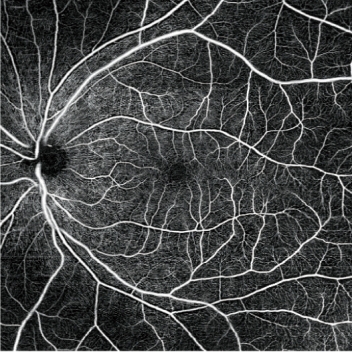

- 高分辨率AngioScan血流OCT圖像

AngioScan(可選軟件)

詳細(xì)信息可在AngioScan頁面獲取。